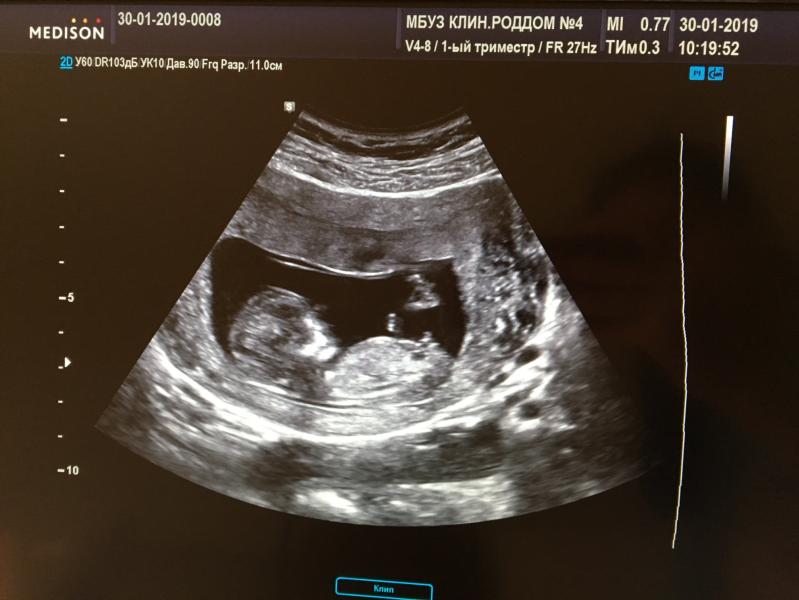

Сходили мы на первый скрининг , посмотрели с третьего раза только 😂😂 Капризуля🙈🙈(наверное девочка) Так волнительно , будто первый раз 😍😍 У вас какие ощущения девочки, делитесь впечатлениями 😊😊